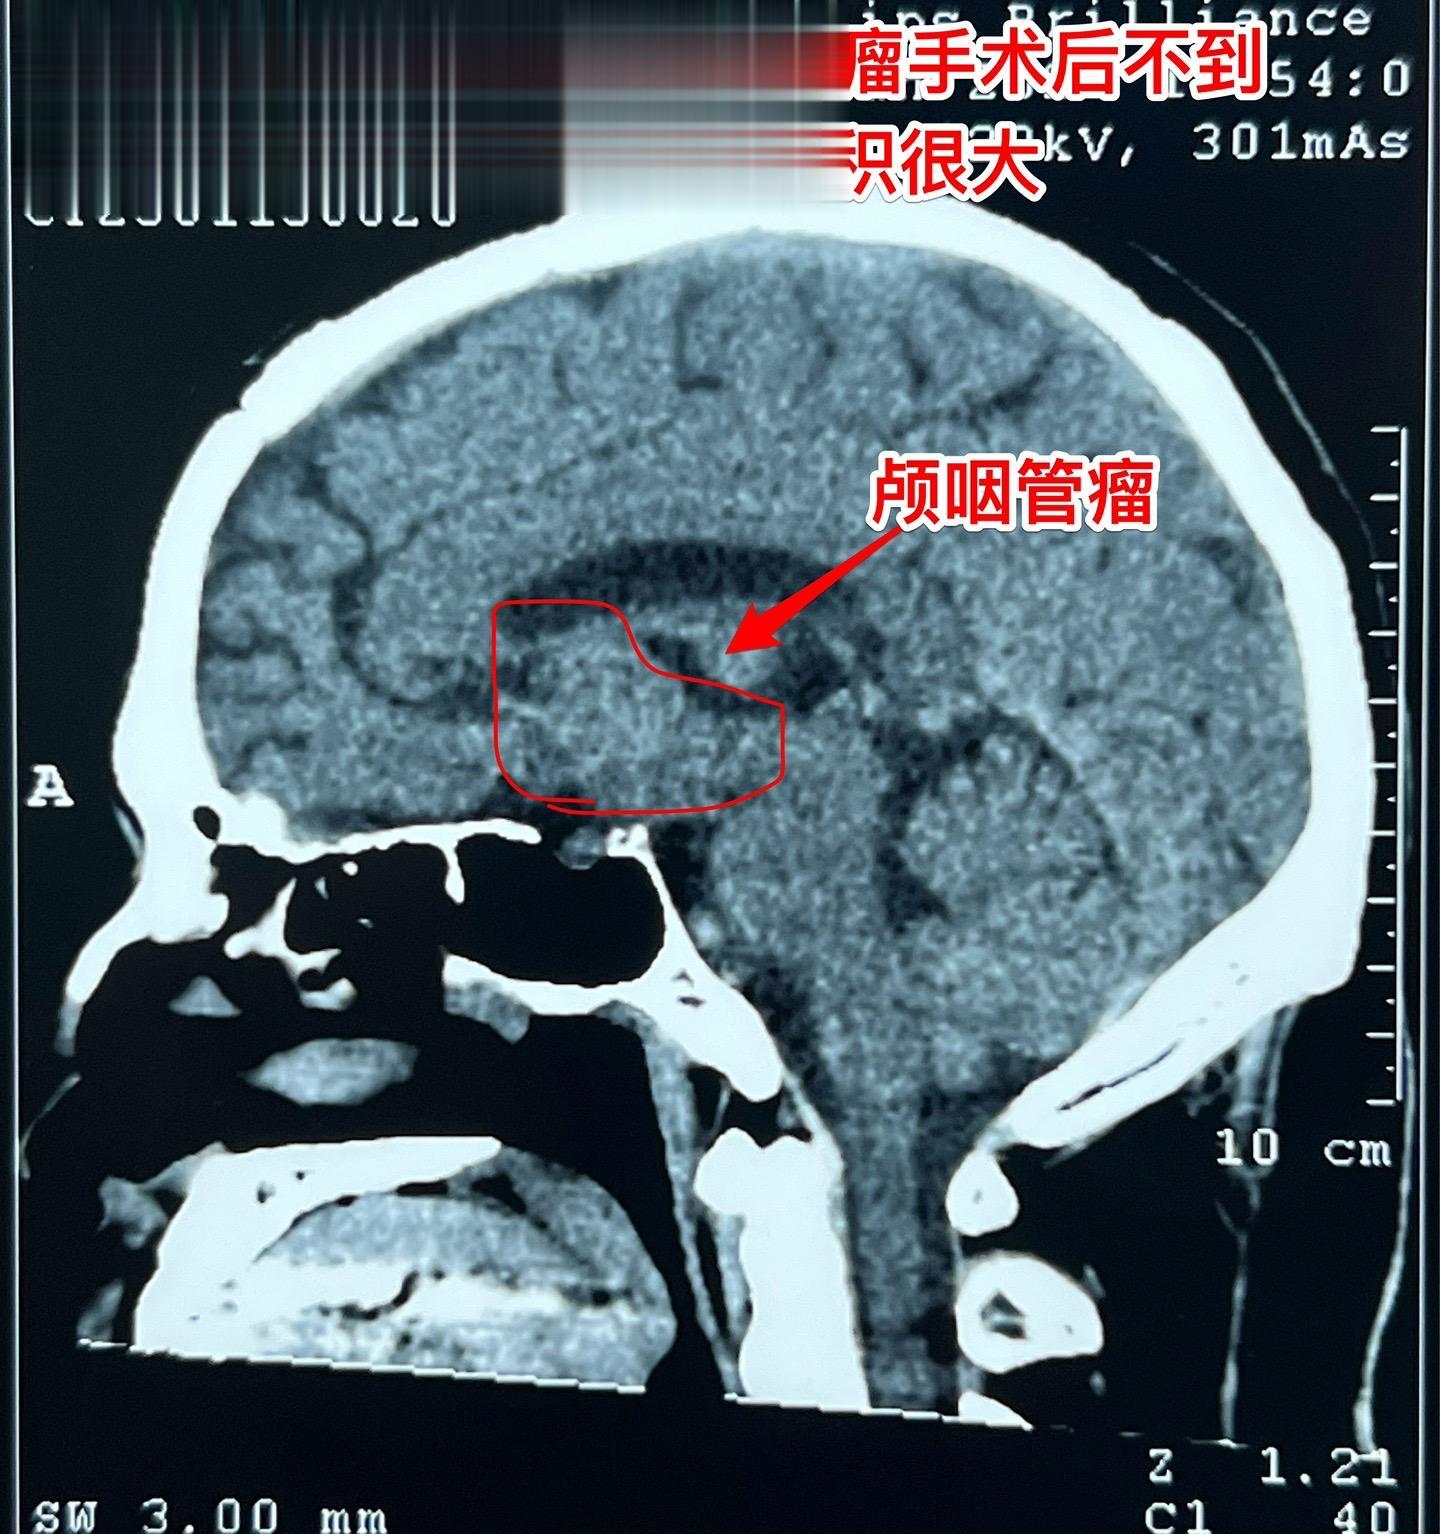

48岁律师,颅咽管瘤术后三个月复查。律师在四川凉山工作,在四川某医院手术未满三个月,自手术后就有记忆力差、爱睡觉等体积症状,难以胜任律师工作。复查磁共振显示颅咽管瘤体积仍然很大,怀疑为肿瘤复发了。 患者家人治病心切,直接到北京找我做手术。 今天是腊月二十四,还有5天就过年了。今天为律师作了开颅手术,将肿瘤完全切除了。希望颅咽管瘤不再复发。